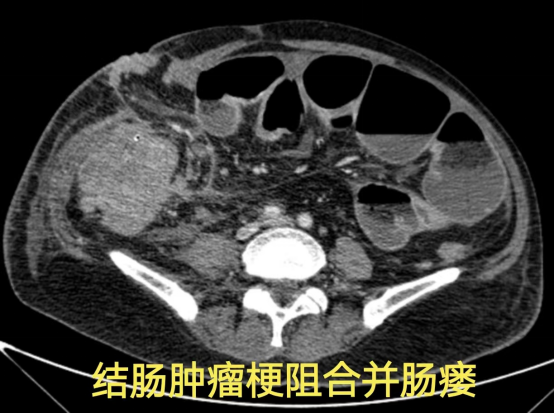

病情简述:60 岁男性,结肠癌肝肺转移,经历多线治疗后并发肠梗阻、肠造口术后出现严重腹腔感染、重度营养不良。

诊疗破局: 面对肿瘤压迫、感染、营养不良三重打击,团队未轻言放弃。从精细化的伤口缝合入手,先为患者创造手术条件;最终通过多学科协作,一次性完成「肿瘤切除+感染清理+腹壁重建」的高难度手术。

技术体现: 在极端复杂的晚期肿瘤并发症面前,系统的整合救治能力是逆转危局的关键。